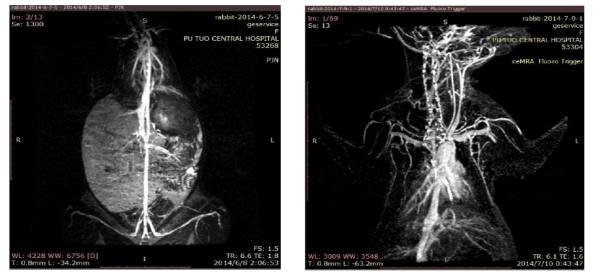

血管造影: